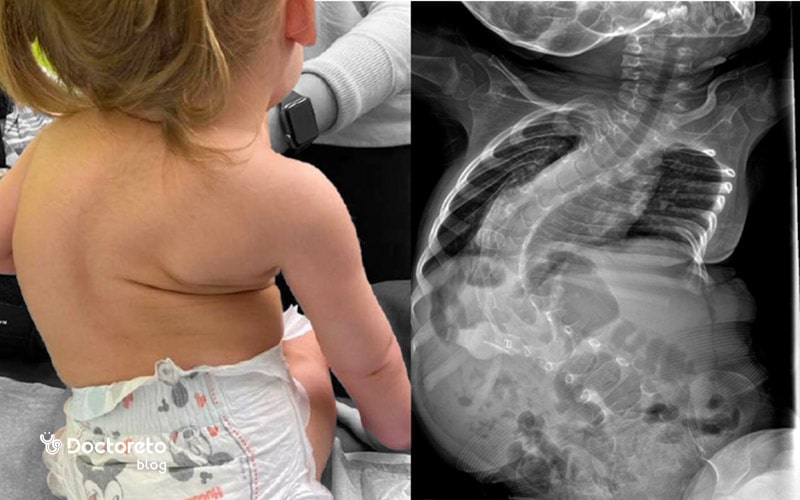

- اسکولیوز (انحنای ستون فقرات)

بیماری اس ام ای نوع دو که به آن اس ام ای متوسط هم میگویند، معمولا در سنین 6 تا 18 ماهگی ایجاد میشود و همه چیز قبل از این دوره، عادی است. در این نوع از بیماری کودکان ممکن است بتوانند بنشینند و مشکلی در حرکت دادن سرشان ندارند، اما چالشهای تنفسی میتواند با پیشرفت بیماری، عمر بیماران را کوتاه کند. آنها در ایستادن بدون کمک مشکل دارند. انحنای ستون فقرات (اسکولیوز) محتمل است. علائمی مانند لرزش دستها و مشکلات رشدی از مشکلات رایج کودکان مبتلا به نوع دو این بیماری است.

- مشکلات استخوانی و مفصلی مانند اسکولیوز